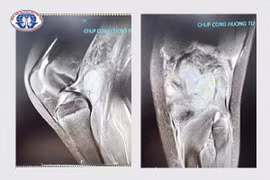

Bị u nhọt ở chân, cậu bé 10 tuổi ở Tân Sơn được người nhà cho đắp thuốc dân tộc không rõ nguồn gốc nhưng tình trạng ngày càng nặng hơn, bị áp xe vùng khoeo chân, nguy cơ để lại di chứng khó khăn trong vận động chi dưới.